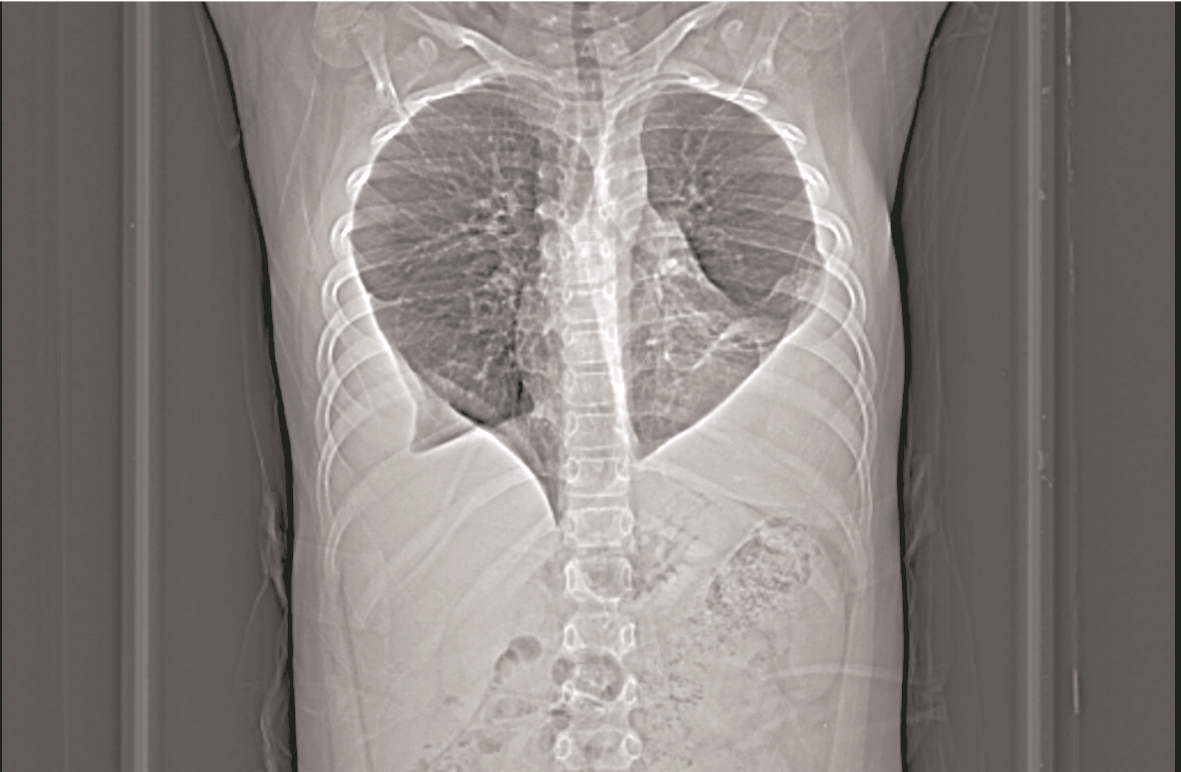

一般人的肺是饱满的树叶形,而11岁男孩嘉嘉(化名)的肺却是桃心形。

拍片发现,嘉嘉的肺部形态跟正常人完全不同——正常人的肺像两片饱满的树叶,而他的肺像桃心一般上头宽下头尖,原本属于肺叶下端的部分,则被不明物体覆盖。进一步检查发现,嘉嘉的肺感染了肺吸虫。

武汉儿童医院心胸外科主任皮名安介绍,肺吸虫感染导致嘉嘉的双侧肺都有严重积液,积液在他的肺中不断沉积,积液中的蛋白质等物质,在沉积并钙化后形成“纤维板”,附着于他的肺部下端。慢慢的,嘉嘉正常的肺叶就成了桃心的形状。